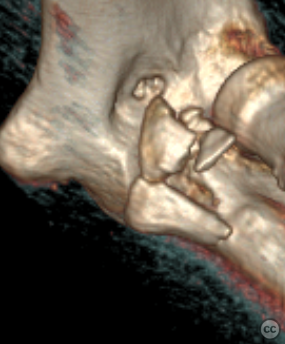

Anteromedial Facet and Sublime Tubercle...

Schleswig Holstein, Germany

Ulna - AO/OTA 2Ux

O'Driscoll type II coronoid fracture dis...

Endobutton fixation of an O’Driscoll ant...

Brussels, Belgium